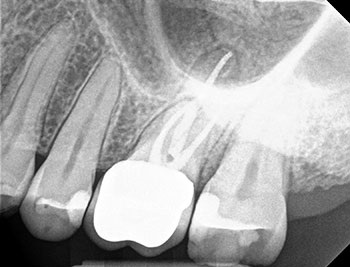

The patient returned in three months, when resolution of symptoms, healing of the deep probing defect and bone regeneration were confirmed. The tooth was obturated, and a foundational restoration was placed before the rubber dam was removed. Fourteen years of follow-up confirmed long-term periradicular health. The amount of appreciation and gratitude that this patient expressed reminds us that each individual tooth demands our best efforts.

Fig. 3: Recall PA.